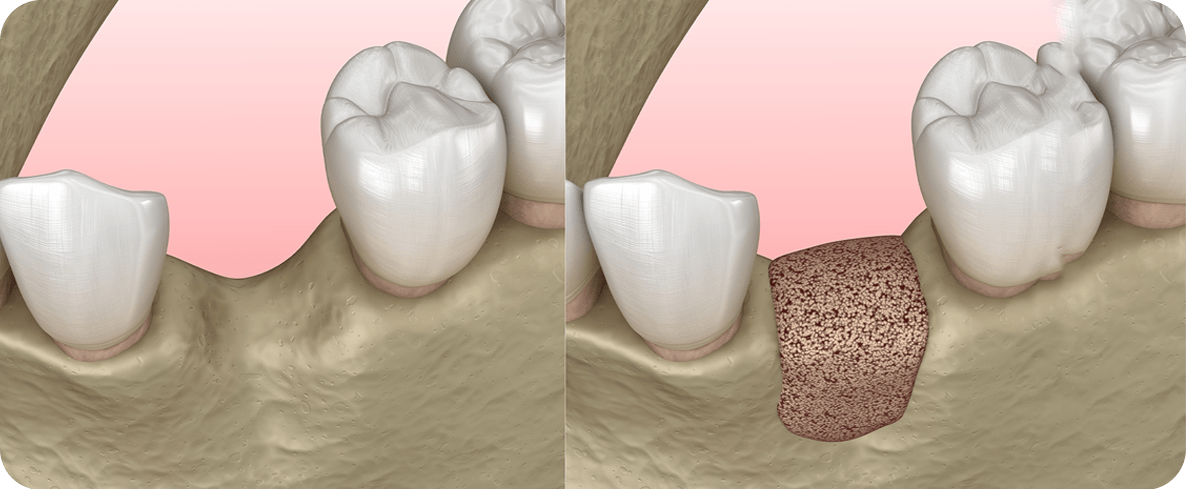

일반 치조골 이식

치조골 흡수로 인해 임플란트를 식립할

잇몸뼈가 부족한 경우 뼈이식재를 이식한 후

골 형성을 유도하고 회복해

안정적인 임플란트를 진행합니다.

치조골 흡수로 인해 임플란트를 식립할 잇몸뼈가 부족한 경우

뼈이식재를 이식한 후 골형성을 유도하고 회복해

뼈이식임플란트 시술과정

잇몸뼈가 소실된 부위에 뼈 이식재를 이식하고

잇몸뼈를 보강한 후 임플란트 식립을 진행합니다.

잇몸뼈가 소실된 부위에 뼈 이식재를 이식하고 잇몸뼈를 보강한 후 임플란트 식립을 진행합니다.